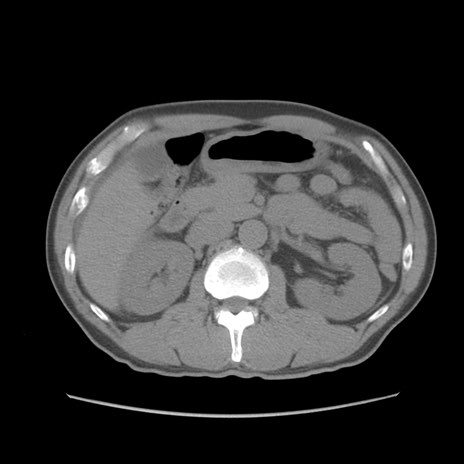

症例56 CT(横断像)

脂肪ウインドウ